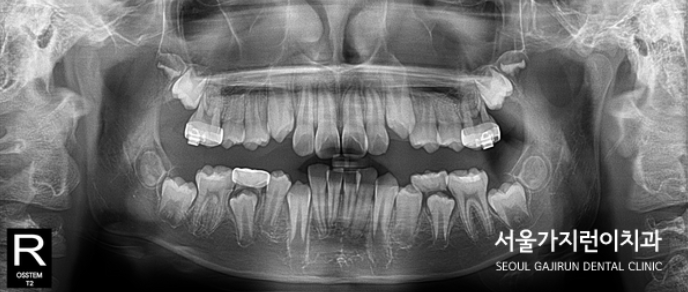

오늘은 상악의 돌출 케이스를 설명해볼텐데요. 치아의 배열 공간이 심하게 부족했던 성장기 환자의 비발치 교정이기 때문에 좀 더 까다로운 교정과정일 수밖에 없었습니다. 환자 분의 경우 상악골의 과성장과 하악골의 열성장이 종합적으로 발현된 케이스로 상악괄의 과성장을 조절하고 상악 견치 및 소구치의 맹출 공간을 확보하기 위해 상악 어금니의 후방이동이 필요했는데요. 그 과정에서 헤드기어라는 장치를 이용한 치아교정이 이루어졌습니다.

이후에는 돌출감을 해소하기 위한 미니스크류를 활용한 치아교정이 이루어졌는데요. (미니스크류는 잇몸에 박혀있는 작은 나사와 같은 장치를 말합니다. ) 미니스크류는 간단한 국소마취로도 식립이 가능하고 잇몸뼈에 직접 식립하기 때문에 강력한 고정힘으로 정밀하게 치아이동이 가능한데요. 치료를 하지 않았다면 치아의 배열이 심하게 비뚤어지고 상악 전치가 뻐드러졌을 것을 1차 성장교정(헤드기어)를 통해 만족할 수 있는 경과를 만들어냈습니다.